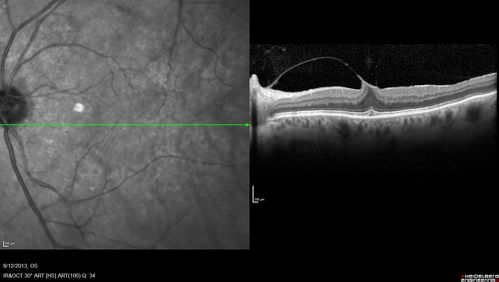

Macular Hole Left Eye - progression from VMT - Stage II macular hole - Spontaneously Closed Macular Hole

Asymptomatic VMT OS with 20/30 VA